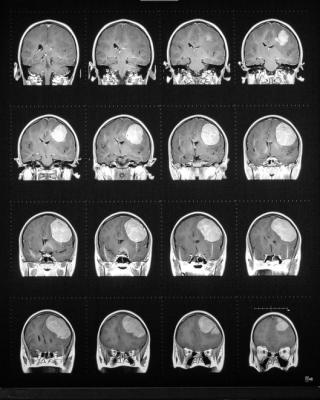

Additionally, the "Elucirem | The Reveal Image Challenge" "Image of the Year" winner will be announced and unveiled at the Guerbet booth at RSNA on Monday, November 27 at 11:00 a.m. CST. The challenge, which was developed in partnership with Applied Radiology, provided MR imaging professionals with an opportunity to reveal their MR imaging potential and to share their MRI images using Elucirem™ (gadopiclenol) injection. A series of winning images were selected each month starting in May 2023, having been evaluated by a review committee, including MRI thought leaders and educators, Applied Radiology board members and Guerbet associates. Winning images were featured on the Applied Radiology website and social media platforms. All winning images will be available for viewing at the Guerbet RSNA booth.